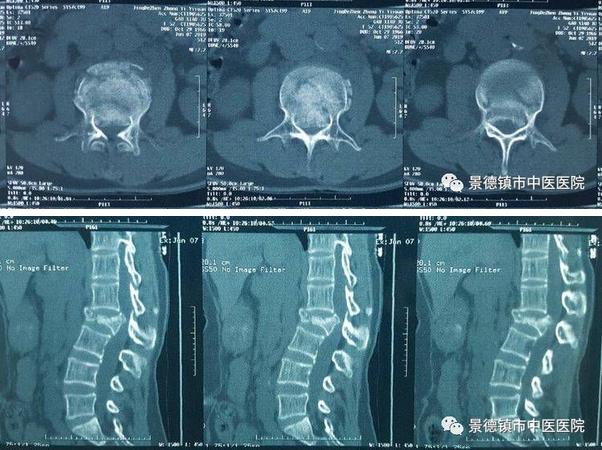

在臨近中午的時候,突然又來了一個腰部外傷的病人,患者L2椎體嚴(yán)重壓縮爆裂性骨折,脊髓受壓嚴(yán)重,下肢出現(xiàn)了麻木肌力減退等截癱癥狀?!摆s快做好術(shù)前檢查及準(zhǔn)備,這個需要急診手術(shù)”,一聲令下,所有人又要更加的忙碌了。于是,為了挽救一個面臨著癱瘓可能繼續(xù)加重的病人,下午又增加了一臺腰椎骨折急診復(fù)位并脊髓減壓手術(shù)了。同時也給手術(shù)室麻醉科、檢驗科等相關(guān)科室增加了假日的工作負(fù)擔(dān),在此也特別感謝大家的支持與配合。